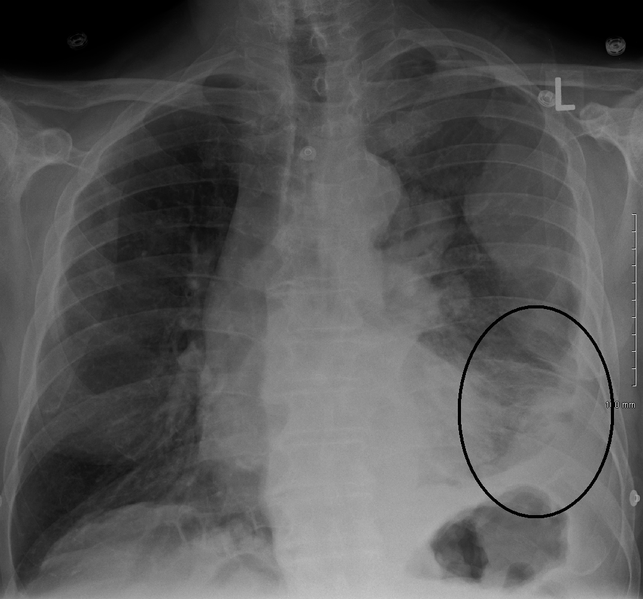

Pleural mesothelioma symptoms, stages, and survival rate. Pleural mesothelioma definition pleural mesothelioma is a cancer caused by asbestos exposure, affecting the pleura lining around the lungs, and it is the most common type of mesothelioma. Pleural mesothelioma accounts for nearly 75 percent of all diagnosed cases of mesothelioma. It is often not diagnosed until decades after exposure to asbestos.

Surviving mesothelioma what you need to know. Learn about mesothelioma cancer types, signs & symptoms, treatment & more! Malignant mesothelioma american cancer society. And obtain benefits. Malignant mesothelioma treatment national cancer institute. Treatment for malignant mesothelioma may include surgery, radiation therapy, and chemotherapy, as well as targeted therapy. The type of treatment you receive depends on where the cancer is found and at what stage. Find out about treatment options for malignant mesothelioma. Mesothelioma cancer research uk. Mesothelioma. Mesothelioma is a cancer that most commonly starts in the layers of tissue that cover each lung (the pleura). More rarely it starts in the layer of tissue in the abdomen that surrounds the digestive system organs (the peritoneum). Mesothelioma symptoms, causes, and prognosis explained. Mesothelioma definition mesothelioma is a rare and aggressive cancer that affects the lining of the lungs, abdomen, and heart. It is usually caused by exposure to asbestos. Pleural mesothelioma affects the tissue around the lungs and is the most common form of this kind of cancer. Latest clinical trials mesothelioma experts top cancer centers.